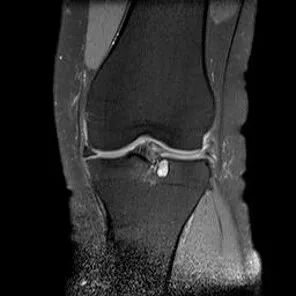

桶柄状撕裂MRI表现

1、宽度减小,在通过半月板体部的冠状面上蝶形消失,同时可见内移的半月板位于髁间窝、交叉韧带旁2、矢状面示残余的前角或后角变小或截断3、半月板前(后)角增宽或双半月板前(后)角征4、双前交叉韧带或双后交叉韧带征

桶柄状撕裂:宽度减小,在通过半月板体部的冠状面上蝶形消失,同时可见内移的半月板位于髁间窝、交叉韧带旁

桶柄状撕裂:半月板后角增宽

半月板撕裂:桶柄状撕裂(双前角征)

桶柄状撕裂(双后交叉韧带征)

桶柄状撕裂:双前交叉韧带征